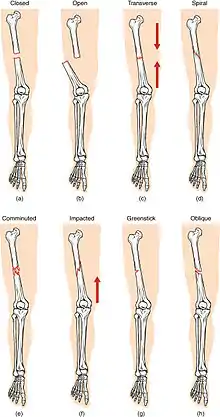

Classification

(a) closed fracture

(b) open fracture

(c) transverse fracture

(d) spiral fracture

(e) comminuted fracture

(f) impacted fracture

(g) greenstick fracture

(h) oblique fracture

In orthopedic medicine, fractures are classified in various ways. Historically they are named after the physician who first described the fracture conditions, however, there are more systematic classifications as well.